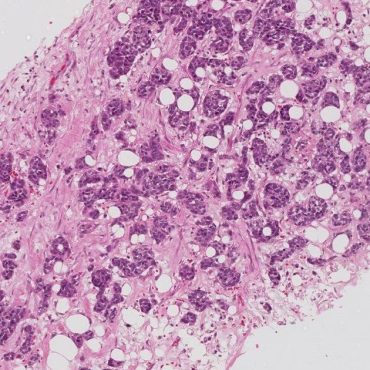

Over the past few years, Roberto Salgado, Sherene Loi and Carsten Denkert have developed the International Immuno-Oncology Biomarker Working Group on Breast Cancer, with members including expert clinical research groups, pathologists, clinicians and statisticians worldwide currently knowledgeable in the field of Immune-oncology Biomarkers. The purpose of this Working Group is to develop, in a timely manner, standards on the assessment of Immuno-Oncology Biomarkers to aid pathologists, clinicians and researchers in their research and daily practice.

All materials on this website, including images, annotations, and similar research and educational data, are anonymized and are therefore freely available to browse, download, and use for scientific and educational purposes.

The group has worldwide representatives of known clinical research groups from high level expert centers across all continents (US, EU, the Middle East and Japan) like the MD Andersen Cancer Center (US), Weill Cornell University (US and Qatar), Memorial Sloan Kettering Cancer Center (US), Dana Farber Cancer Institute (US), Peter Mac Callum Cancer Center (Aus), Insitut Gustave Roussy (EU), European Institute of Oncology in Milan (EU), Jules Bordet (EU), National Cancer Institute, Lima (South America), etc..